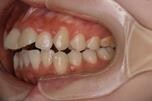

開咬を主訴に来院されました。診断したところ、改善点が大きく4つに分けられます。

②前歯の開咬

これは文字通り、前歯が噛み合わずに隙間が開いている状態です。奥歯は当たっているのに、前歯(中切歯・側切歯)が上下でスカスカに空いていることです。隙間が何ミリあるかによって、インビザラインで「歯をどれだけ垂直に伸ばす(圧下・挺出)」必要があるかを判断します。重度の場合は、骨格の問題も疑われます。